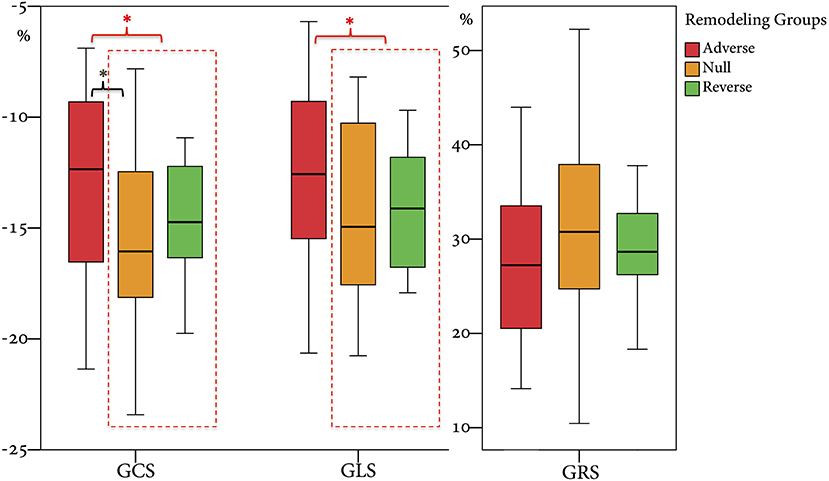

From 2010 to 2019, a total of 1,285 STEMI patients underwent pPCI in Policlinico Umberto I Hospital, of which ~15% had CMR performed and 78 were recruited as reported in the flow chart (Figure 1). According to our internal procedures, when allowed by the clinical condition of the patient, the availability of the scanner/staff, and in the absence of contraindications, CMR was performed in reperfused STEMI patients for the assessment of post-infarction myocardial injury during the acute phase and to detect complications at short and long term follow up. Among the study population of enrolled STEMI patients, 38 (49%) showed adverse, 22 (28%) reverse, and 18 (23%) null LV remodeling, assessed by paired CMR exams (baseline and FU-CMR). Demographic, clinical, angiographic, and pharmacological characteristics of the STEMI population according to the three groups are illustrated in Table 1. No differences in demographic data, cardiovascular risk factors, angiographic presentation, or laboratory findings were found. Agreement in strain measurements was excellent with ICC between 0.922 and 0.943 (p < 0.001, Supplementary Material) and p > 0.43 (range 0.43–0.85) at Wilcoxon's test. Regarding pharmacological therapy, no differences were noted about beta-blocker, antidiabetics, statins, ACE-inhibitors, spironolactone, GbIIb-IIIa inhibitors, and clopidogrel use among the three LV remodeling categories, except for the pre-pPCI ASA administration. At the first CMR exam, patients with LV adverse remodeling showed higher AAR, IS, and MVO, if compared to the other two groups (Table 2). Meanwhile, at FU-CMR, the adverse remodeling group had lower LVEF, greater IS extent, and lower LV-RI. At CMR strain analysis, significantly worse GCS and GLS values at baseline and FU-CMRs in the adverse LV remodeling group, compared to the sum of the other two groups, were found (Figure 2, Table 2). After adjusting for age, sex, BMI by ANCOVA analysis, the only CMR derived parameters that reported a different statistical significance if compared with ANOVA analysis, according to the three remodeling groups, were baseline AAR, baseline MVO, FU IS, baseline GRS, and baseline GLS.

Figure 2. Comparison of GRS, GCS, and GLS values according to the three remodeling groups. GRS, global radial strain; GCS, global circumferential strain; GLS, global longitudinal strain. * symbol indicates statistically significant comparisons among groups. *p < 0.05.

In this study, we categorized the population using the three LV remodeling patterns based on Bulluck's definition (7), observing a similar percentage distribution (adverse remodeling 49 vs. 45%, reverse remodeling 28 vs. 29%, and null remodeling 19 vs. 23%). For CMR parameters, the adverse remodeling group showed greater AAR, IS, and MVO at baseline CMR and greater IS at FU-CMR, as already reported (7). Otherwise, no differences in IS and MVO between reverse and null remodeling groups were found in our study. Notably, there were no differences in salvage myocardium extent among the three groups. Although IS and MVO are known predictors of adverse remodeling (7), the relationship between them and myocardial recovery is still an open issue (6, 7). Moreover, at FU-CMR, the adverse remodeling group showed lower LVEF, LV-RI, and greater IS, as compared to the other two groups. Regarding FT-CMR strain analysis, the adverse remodeling group showed worse GCS and GLS values at baseline and FU-CMR (Figure 5), if compared to reverse and null remodeling categories as one. Various studies investigated the value of FT-CMR features in predicting adverse remodeling (11, 12, 22), using different cut-off values and follow-up periods. For the definition of adverse LV remodeling, we considered LVEDV and/or an LVESV delta change of 12%, which is lower than most reports, and 6 months for follow-up, longer if compared to other studies, mostly around 3/4 months. Thus, this issue may have induced a larger rate of adverse remodeling in our population (49%), as compared to other cohorts (17–24.4%) (11, 12, 22, 23). In the majority of studies, baseline GLS was the best predictor of adverse remodeling among all strain values (11, 22–24). In particular, Reindl et al. (22) reported significant differences in baseline strain values and infarct size/MVO percentage between no remodeling and remodeling groups, as observed in our cohort. Moreover, they showed that a GLS-value > −14% was the best independent predictor of 4 months LV adverse remodeling (LVEDV delta change of 10%) with an AUC of 0.610, which do not differ substantially from our GLS AUC value of 0.639 using LVEDV/LVESV delta change of 12%. In the retrospective study of Cha et al. (11), at ROC curve analysis (AUC: 0.756, 95% CI = 0.636–0.887, p < 0.001), the GLS cut-off of −12.84% resulted in high sensitivity (Se: 85%) and low specificity (Sp: 61%) in predicting adverse remodeling at 6 months (LVEDV delta change of 20%), whereas in our study the optimal cut-off was lower (GLS > −10.21%), with lower sensitivity (Se: 35%) and higher specificity (Sp: 90%), likely reflecting the different criteria in classifying the remodeling groups. Interestingly, in our study GCS was the strongest predictor of adverse remodeling among the baseline strain values, as already reported by other authors (12, 25, 26). Holmes et al. (12) found that GCS was a superior predictor of LV adverse remodeling at 3 months follow-up than MVO, GLS, and GRS, although they considered a cohort of both STEMI and non-STEMI patients (12), differently from our population of STEMI only. Similarly, Buss et al. demonstrated that GCS is useful in predicting preserved LV function at 6 months follow-up but they did not evaluate LV remodeling groups (25).